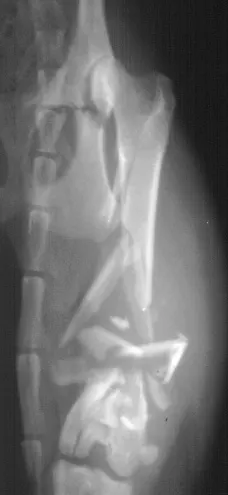

The interlocking-nail system (Innovative Animal Products, Rochester, MN) is another effective implant system for biologic management of comminuted fractures in dogs and cats.1 The interlocking nail is a modified Steinmann pin having transverse holes designed to accommodate screws or bolts. The addition of screws or bolts increases the ability of the pin to resist rotational and compressive forces at the fracture site (Figures 2A, B). This type of fixation is commonly used for stabilization of fractures of the femur and tibia in humans.

Interlocking nails are used in dogs and cats for repair of fractures of the humerus, femur, and tibia. The interlocking-nail system is less expensive than a bone-plate system but has similar biomechanical properties.8 Interlocking nails are easy to apply and are a good option for general practitioners who do not want to invest in a bone-plate system.

Fractures managed using interlocking nails and biologic technique develop extensive bridging callus and early return to function. A minimally invasive surgical approach (note the surgical skin staples) was made to this fracture to minimize disruption of the blood supply to the bone fragment. The fracture fragments quickly become incorporated in the callus if soft tissue attachments can be maintained.

Healing of the comminuted tibial fracture shown in Figures 2A and 2B after stabilization using an interlocking nail system. This fracture reached bony union in 8 weeks.